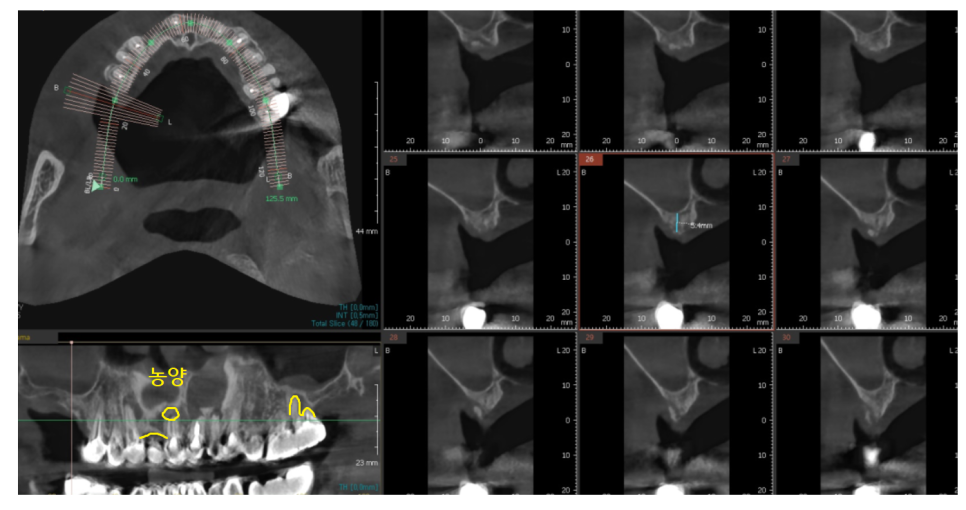

23.06.07

큰 사진에서 의심되는 부분을

추가적으로 검사해 보았더니

어이쿠야..

뿌리 끝에 농양으로

주변 뼈가 녹았네요.

이미 신경치료까지 되어있는 상황이라

좋지 않았지만

살려볼 수 있는 1% 가능성이라도

확인하기 위해 ct까지 찍어보았습니다.

주변 잇몸뼈가 이미 다 녹아있어

그대로 둬도 좋을게 없었습니다.

옆에 치아 잇몸뼈까지 녹일 수 있는 상황이었거든요.